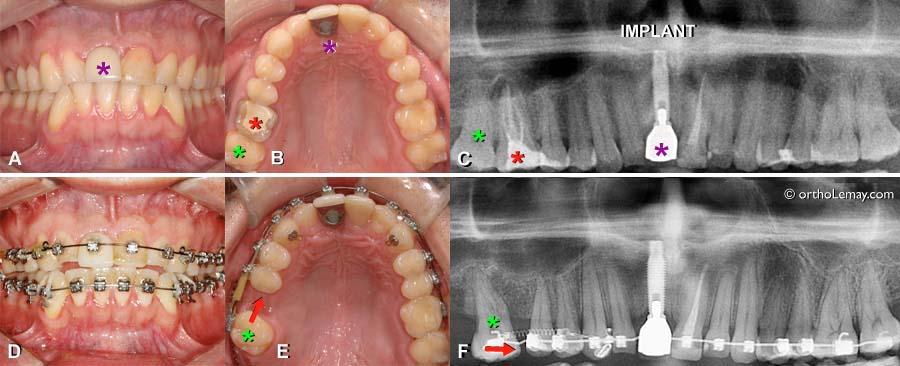

Apparition de caries entre des dents antérieures pendant l’orthodontie-1

(A et B) La rotation de deux centrales camoufle une carie entre ces dents. (C) La carie est visible vue de l’intérieur de la bouche. (D) Après les corrections orthodontiques et la réparation de la carie.